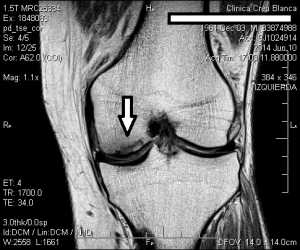

El 10/10/2014 se intervino J.C de 53 años de edad con una necrosis de condilo femoral interno. Desde hacía unos meses realizaba tratamiento de R.F., AINES y marcha con muletas para no efectuar carga de peso con la rodilla afectada. Al examen físico se observaba rodilla con derrame articular, dolorosa a la palpación (especialmente en interlínea interna femorotibial, coincidente con la necrosis), y posición viciosa en flexión. Evitaba la carga de peso por prescripción médica.

La mejoría sintomática fué casi inmediata y la evolución se hizo evidente en la RM el 4/12/2014, en menos de dos meses de realizado el tratamiento con implantes de oro. El paciente tenía unas perspectivas (según los médicos tratantes) de una baja laboral de muchos meses, con una gran incertidumbre respecto a su futuro laboral, y con un pronóstico incierto de su capacidad laboral.

A continuacion se observan las imágenes más significativas: